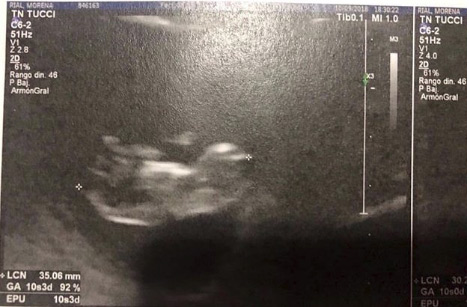

Luego de una confirmación y una inmediata desmentida, la hija mayor de Jorge Rial anunció la noticia de que espera su primer bebé, fruto de su relación con Facundo Ambrosioni.